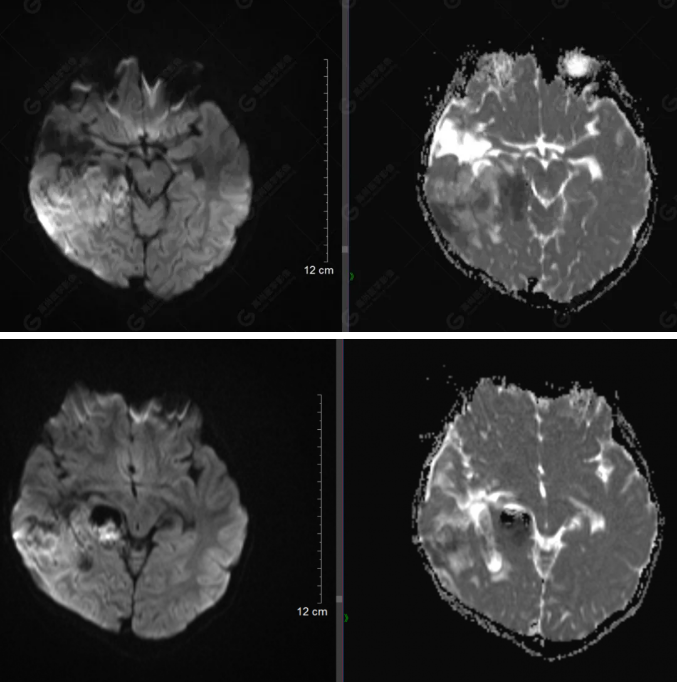

右側(cè)顳葉腫瘤切除術(shù)后(具體不詳):右側(cè)顳部骨質(zhì)不連續(xù)呈術(shù)后改變,右側(cè)顳葉術(shù)區(qū)見(jiàn)片狀長(zhǎng)T1長(zhǎng)T2信號(hào)影,F(xiàn)LAIR呈低信號(hào);術(shù)區(qū)后方右側(cè)顳枕葉見(jiàn)一巨大占位性病變影,邊界欠清,大小約6.2×5.8×4.3cm(前后×左右×上下),信號(hào)不均勻,T1WI呈等稍低信號(hào)間雜少許高信號(hào),T2WI呈高稍低混雜信號(hào),DWI示部分病灶彌散受限,相應(yīng)ADC圖減低,磁敏感序列見(jiàn)部分呈極低信號(hào),增強(qiáng)掃描可見(jiàn)明顯不均勻強(qiáng)化,鄰近硬腦膜及小腦幕增厚并明顯強(qiáng)化;另延髓右前方及右側(cè)橋小腦角區(qū)見(jiàn)一不規(guī)則形異常信號(hào)影,大小約3.2×1.3×3.7cm(左右×前后×上下),呈長(zhǎng)T1稍長(zhǎng)T2信號(hào),F(xiàn)LAIR呈等信號(hào),DWI未見(jiàn)受限,增強(qiáng)后明顯均勻強(qiáng)化,鄰近腦膜明顯強(qiáng)化。鄰近腦實(shí)質(zhì)及右側(cè)顳角明顯受壓;左側(cè)大腦半球未見(jiàn)局灶性信號(hào)異常,中線結(jié)構(gòu)稍左移。

右側(cè)顳葉腫瘤切除術(shù)后:現(xiàn)術(shù)區(qū)后方右側(cè)顳枕葉及延髓右前方占位,右側(cè)顳枕部硬腦膜及小腦幕明顯強(qiáng)化,結(jié)合既往影像資料,考慮為胚胎源性惡性腫瘤,如非典型畸胎樣/橫紋肌樣瘤(AT/RT)或原始神經(jīng)外胚層腫瘤(PNET)。